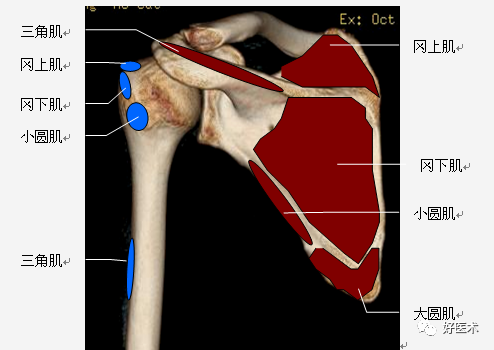

(2)肩袖

肩袖是由冈上肌、冈下肌、小圆肌和肩胛下肌的肌腱构成。前三个肌腱由上向下均止于肱骨大结节,而肩胛下肌腱止于肱骨小结节。

位于冈上肌腱与肩胛下肌腱之间的间隙称之为旋转间隙( rotator interval) 。其内有喙肱韧带、肱二头肌长头腱、上盂肱韧带和喙突。